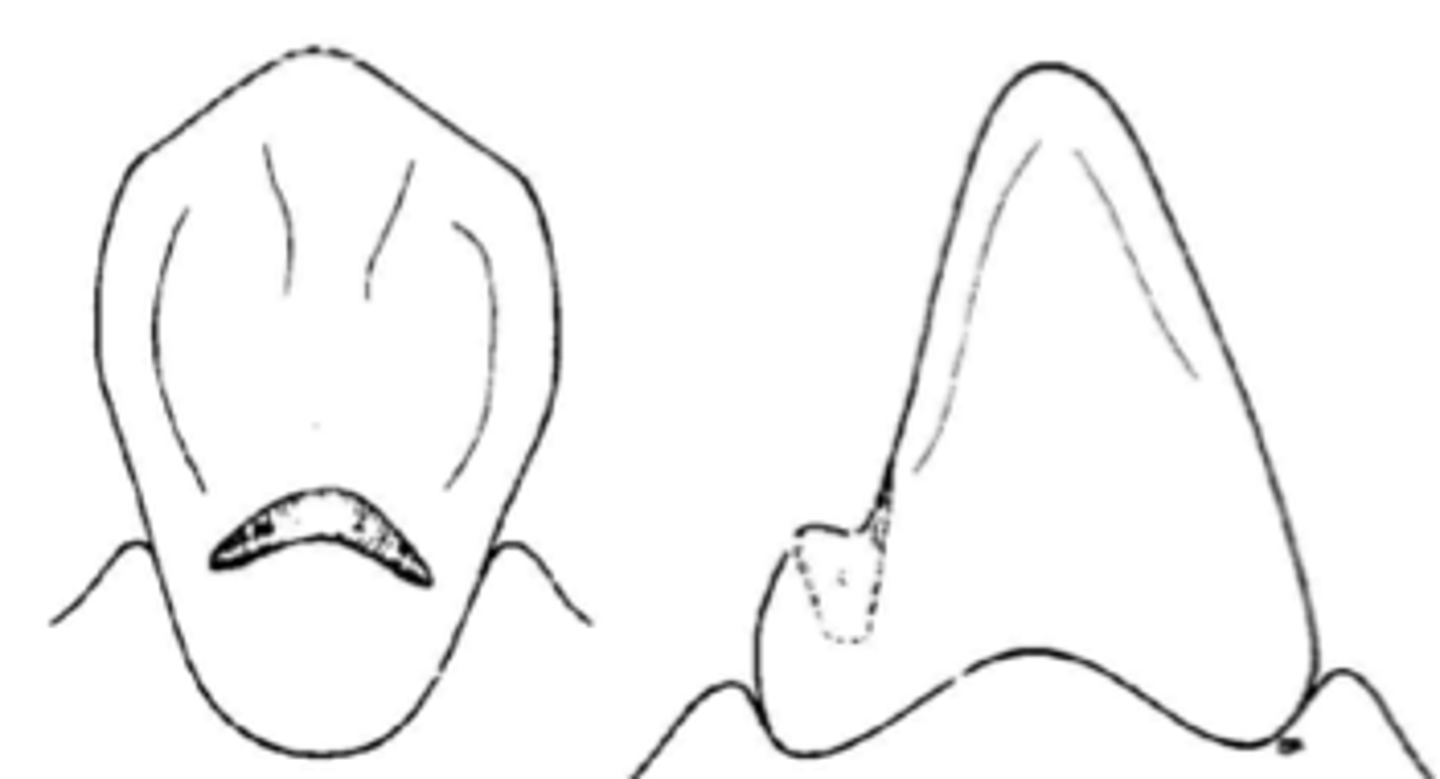

Cingulum rest

Similar to occlusal rests, the rest must be made at the correct angulation in reference to the tooth surface to prevent the rest from sliding away from the tooth.

Rest on a canine

Indirect retainer type when premolars are unavailable or inappropriate)

• Cingulum rest on maxillary canines

• Incisal or cingulum rest on mandibular canines